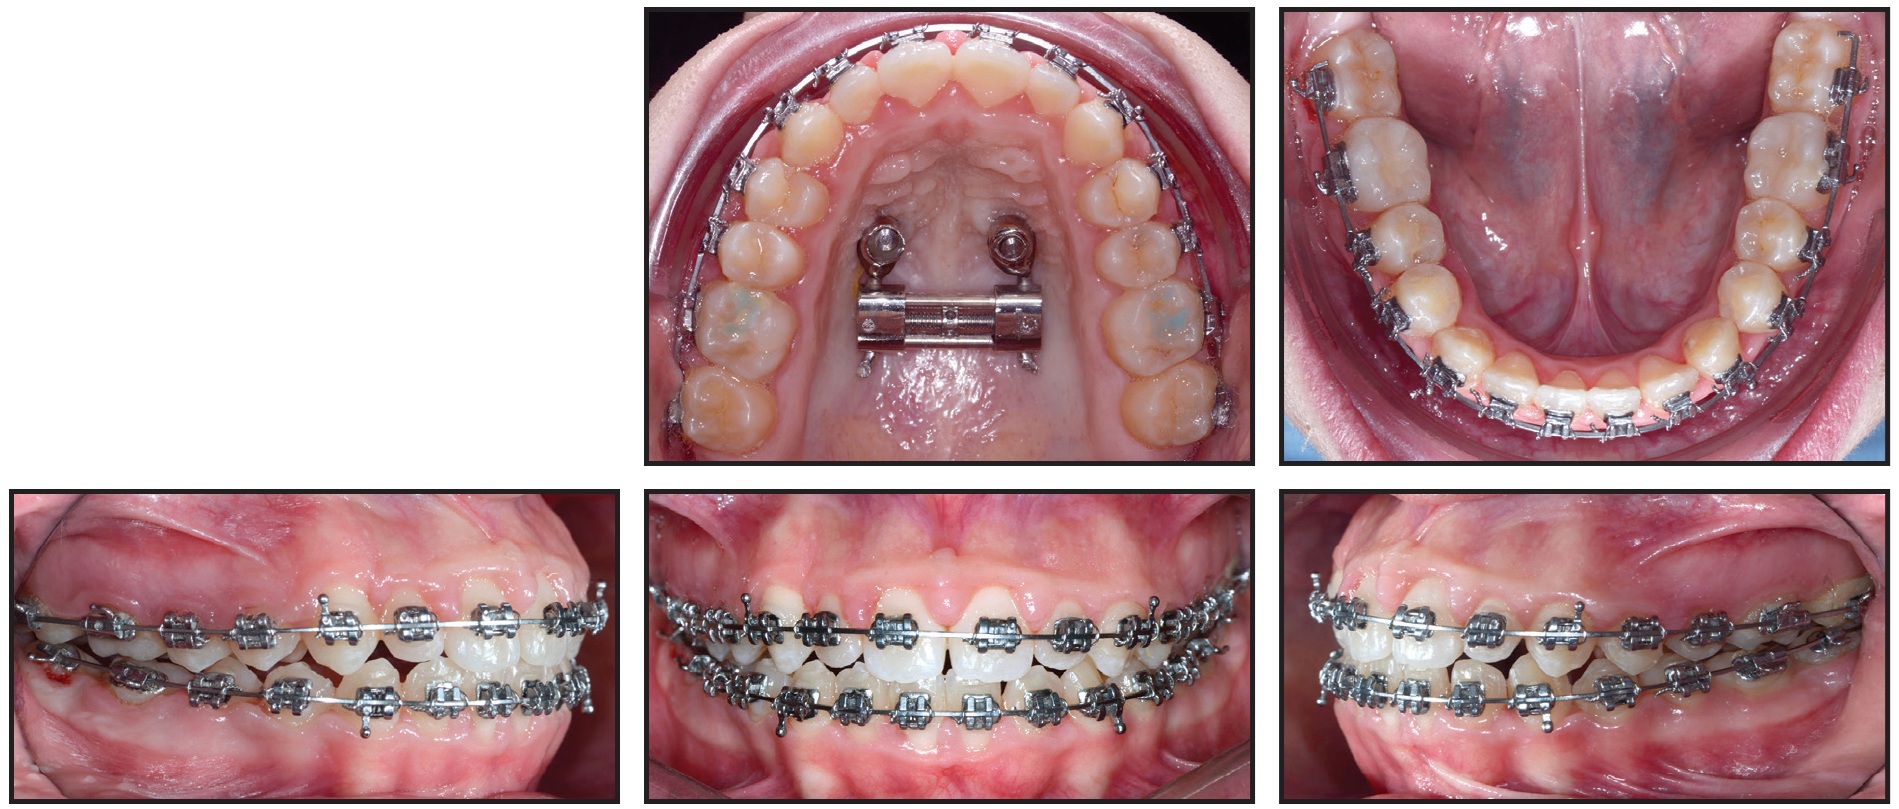

Next, an h-RPE was fabricated, with buccal arms welded to the first-molar bands for attachment of the facemask (Fig. 4). The anterior palatal arms of the RPE were welded to two metal abutments designed to fit over the miniscrew heads, each affixed with a microscrew. After bonding, the h-RPE was activated until the transverse deficiency was corrected (32 days at one quarter-turn per day).

Fig. 4 A. Hybrid rapid palatal expander (h-RPE) with anterior palatal arms welded to metal abutments over miniscrew heads. B. Skeletal maxillary expansion after 32 days (one quarter-turn per day).

Primo** .022" labial brackets were bonded indirectly, and .014" nickel titanium archwires were inserted in both arches (Fig. 7). An open-coil spring was placed between the upper right lateral incisor and first premolar to provide space for eruption of the ectopic canine and to help center the upper dental midline.

Fig. 7 Primo** .022" labial brackets bonded and .014" nickel titanium archwires inserted in both arches; open-coil spring placed between upper right lateral incisor and first premolar to provide space for canine eruption and to center upper dental midline.

Two months later, when enough space had been created for the upper right canine, its eruption was initiated by tying an elastic module to its mesial bracket wings and to the archwire27 (Fig. 8).

After four months of canine alignment, an .019" × .025" nickel titanium archwire was inserted in the upper arch to continue leveling (Fig. 9). An .019" × .025" stainless steel archwire was inserted in the lower arch, with elastomeric chain added to close existing spaces and to prevent unwanted spaces from opening between the lower canines and lateral incisors. For sagittal and anterior vertical correction, the patient was asked to wear ³⁄16", 6oz Class III elastics*** 22 hours per day in a triangular configuration from hooks on the upper and lower canines to hooks on the upper first molars.

Fig. 8 Two months later, with sufficient space gained for upper right canine, eruption initiated with elastic module tied to mesial bracket wings and archwire.

Fig. 9 After four months of canine alignment, upper .019" × .025" nickel titanium and lower .019" × .025" stainless steel archwires inserted, with elastomeric chain added in lower arch for space closure.

Two months later, the brackets on the upper right central incisor and lower right first premolar were repositioned for finishing and detailing, and Class III elastics were applied asymmetrically to center the upper and lower dental midlines (Fig. 10).

Fig. 10 Two months later, brackets repositioned on upper right central incisor and lower right first premolar for finishing and detailing.